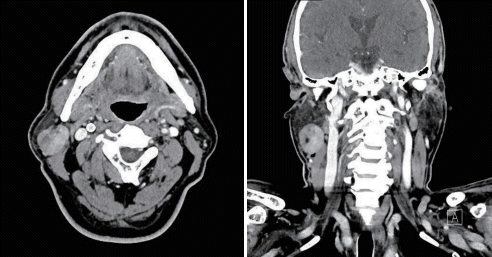

65세 남자 환자가 2년 전부터 만져지는 우측 이하선 종물을 주소로 내원하였다. 내원 당시 우측 이하선에 3 cm 정도 크기의 종물이 촉진되었으며 통증이나 열감은 동반되지 않았다 외래에서 촬영한 경부 전산화단층촬영 소견은 아래와 같았다. 이 질환에 대한 설명으로 옳지 않은 것은?